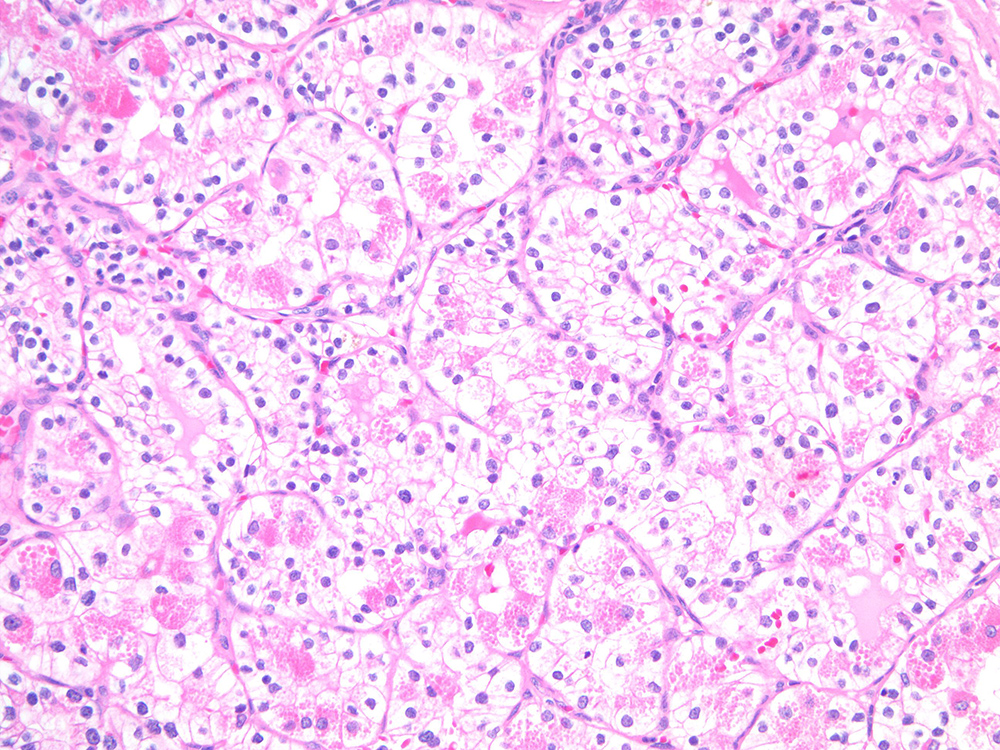

Classification of renal tumors

Case ID: 743